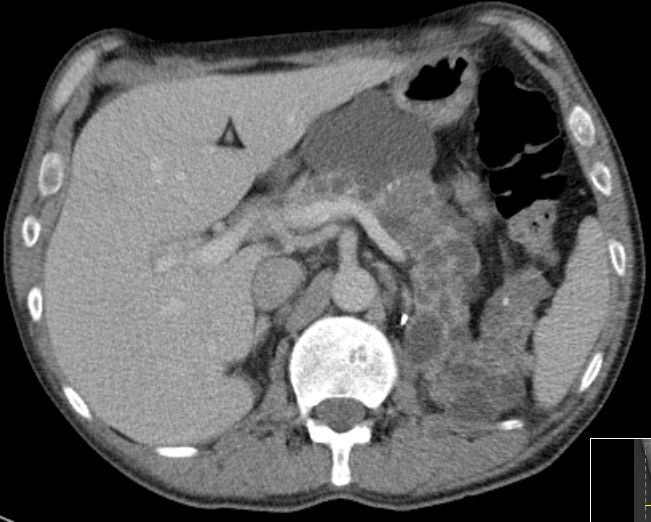

Multiple Pankreaszysten. Nieren beiderseits entfernt.